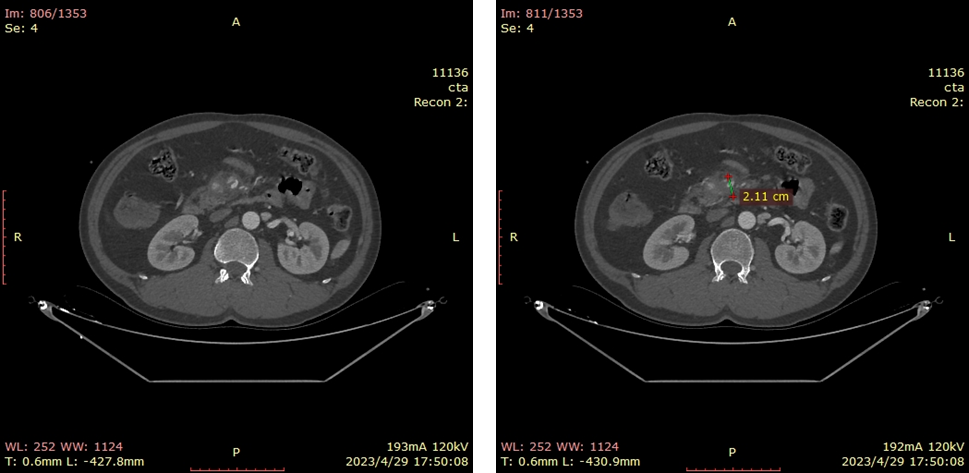

20230515CTA(保守治疗2周我院复查)